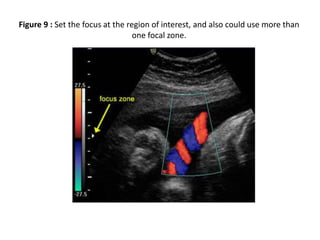

5) Focus: The focus should be at the level of the area of

interest. This can make a significant difference to the

appearance and accuracy of the image

(Figure 9) slides (13/14).

Figure 9 : Set the focus at the region of interest, and also could use more than

one focal zone.

Figure 9 :Set the focus at the region of interest, and also could use more than one focal zone.